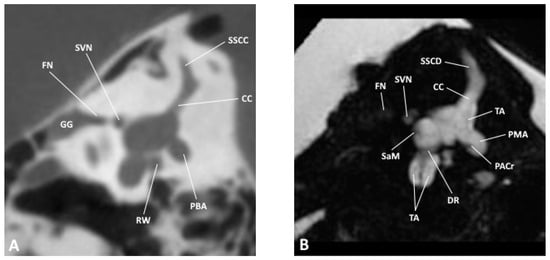

Figure 3. Sagittal slice through the inner and middle ear at the level of the vestibule as observed by (A) CBCT and (B) MRI; CC, common crus; DR, ductus reuniens; FN, facial nerve; GG, geniculate ganglion; PACr, posterior ampullary crest; PBA, posterior bony ampulla; PMA, posterior membranous ampulla; RW, round window; SaM, saccular macula; SSCC, superior semicircular canal; SSCD, superior semicircular duct; SVN, superior vestibular nerve.